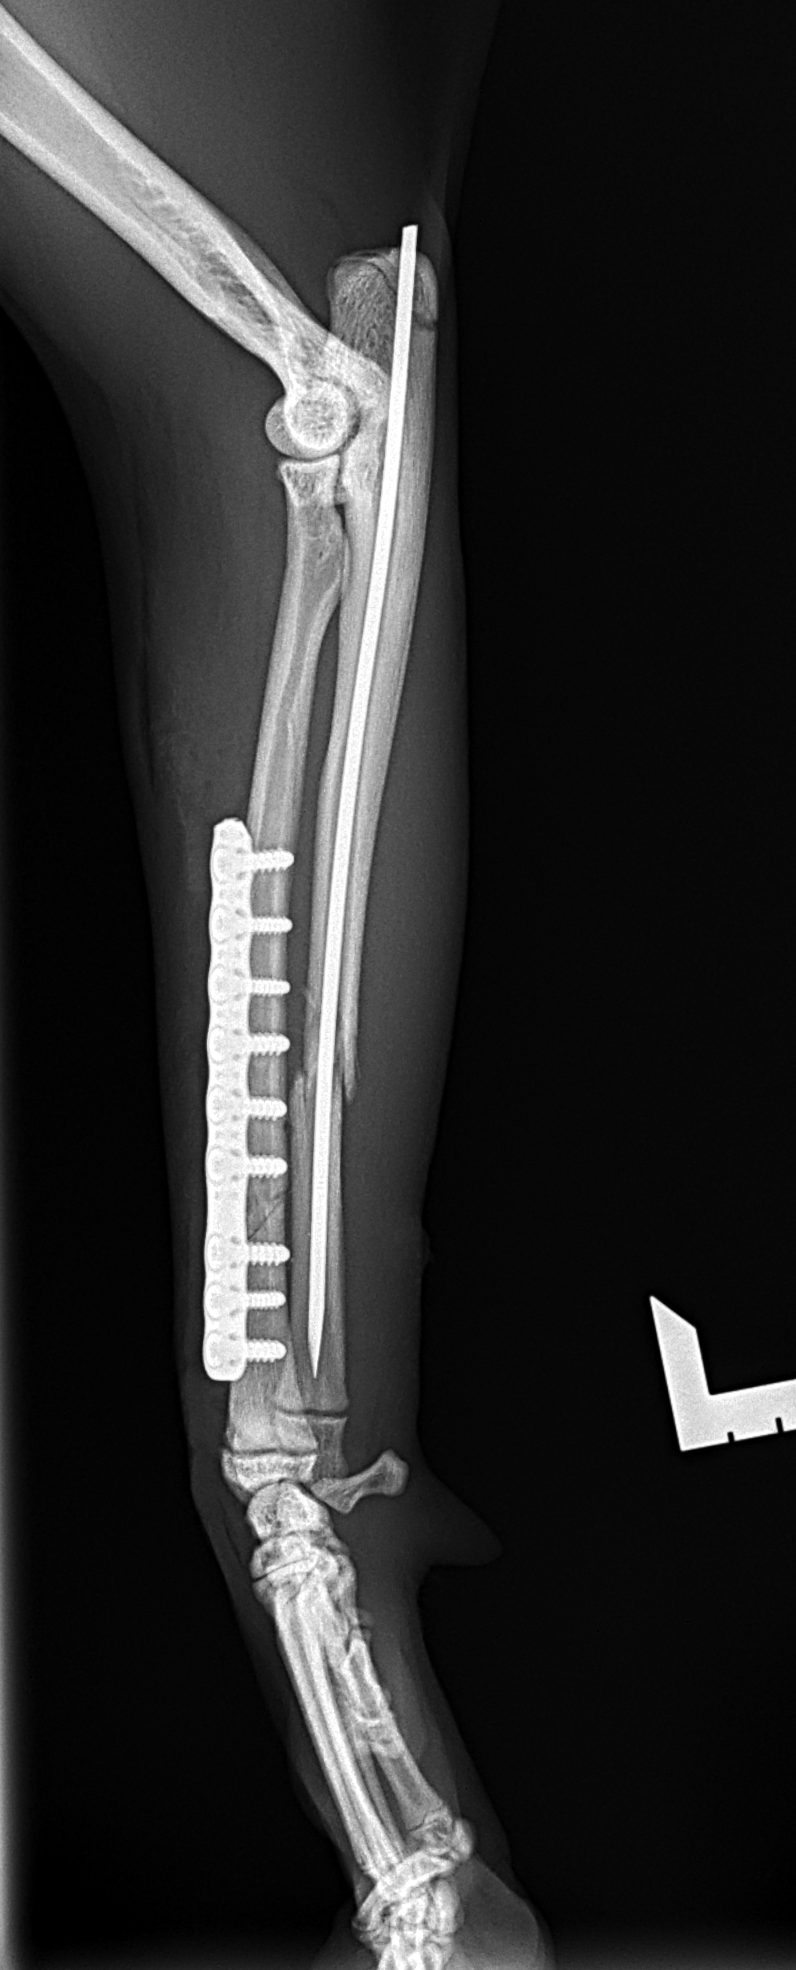

猫さんがご自宅の2Fから落下したとのことで、かかりつけ医を受診されました。右の橈骨尺骨骨折が確認されました。2.4 Titnium Locking Plate(Distal 3holeストレート)、尺骨1.6mm Titanium Wireで固定術を行いました。猫は高いところで遊ぶのが好きな動物なので、遊び場に危険な場所がないか?生活環境を見直す必要があります。